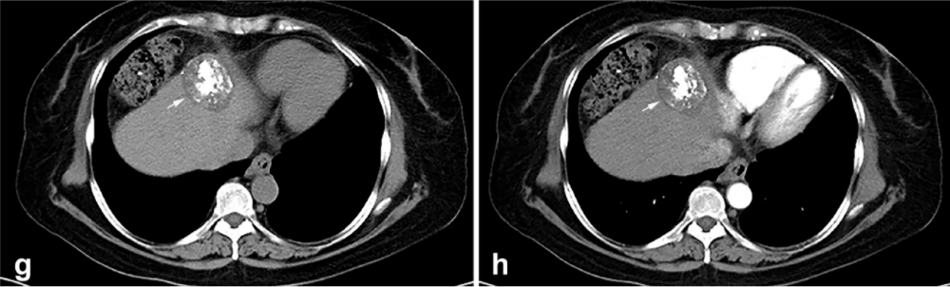

背景:由于一些原因,位于膈肌附近的腫瘤的熱消融在技術(shù)上具有挑戰性。首先,術(shù)中計算機掃描和超聲檢查無(wú)法清晰顯示射頻消融/微波消融切緣。第二,消融過(guò)程中不利的針?lè )植己瓦^(guò)熱可能導致肝包膜破裂,并對膈、肺和心臟造成嚴重損傷。第三,即使使用人工腹水,仍有9~22%的患者因肝周粘連或腫瘤位置靠近肝表面而導致膈肌熱損傷。冷凍消融可能是毗鄰膈肌的HCC的一種有前途的治療方法,因為在消融過(guò)程中使用CT和US可以很好地顯示腫瘤邊緣。盡管一些研究評估了在高危區域使用冷凍消融治療HCC,但很少有研究針對膈肌臨近區域。